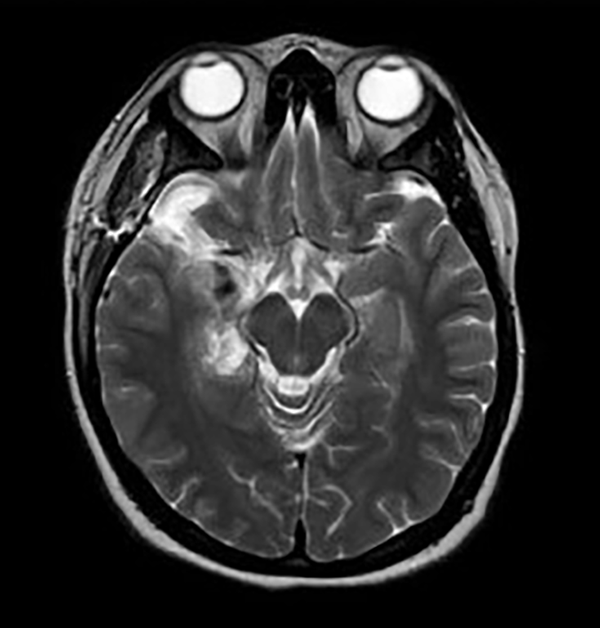

La RM puede identificar lesiones del lóbulo temporal y otras anomalías con una sensibilidad y especificidad de alrededor del 90%. Una amplificación anormal relativa de la señal en la materia gris/blanca del lóbulo temporal, atrofia del fórnix ipsilateral, dilatación del cuerno temporal del ventrículo lateral y desdibujamiento de los límites entre la materia gris y blanca del neocórtex temporal son todos criterios diagnósticos significativos de RM a tener en cuenta. La esclerosis hipocampal del lado derecho se muestra en las Figuras 1A y 1B, y una malformación cavernosa del lóbulo temporal se ve en las Figuras 1C y 1D. Se utilizaron los siguientes procedimientos no invasivos en esta muestra para evaluar a los pacientes antes de la cirugía: RM de 1.5 y 3T, monitoreo de EEG nocturno con video, examen físico neurológico y evaluación semiología. Una vez localizada el área epiléptica, la extensión de la resección quirúrgica fue determinada por electrocorticografía intraoperatoria (ECoG). Además, preoperatoriamente, los pacientes pediátricos se sometieron a evaluaciones neuropsicológicas que incluyeron pruebas estandarizadas adecuadas para la edad para evaluar la cognición, el lenguaje, la memoria, la atención, la resolución de problemas, el análisis visual, espacial, perceptual, habilidades académicas, funciones motoras y sensoriales, comportamiento, personalidad, estado emocional y funcionamiento adaptativo. Se presume el área de disfunción preexistente basada en los datos recopilados, se establece la lateralización de la zona del habla y se evalúan los riesgos y beneficios de la cirugía.4

Figura 1. Esclerosis hipocampal derecha mostrada en las Figuras A y B; y malformación cavernosa del lóbulo temporal en las Figuras 1C y 1D.